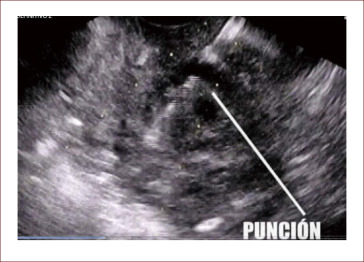

Punción endoscópica

Una investigación con participación del CIBEREHD y liderada por la Unidad de endoscopia digestiva del Servicio de Patologías Digestiva del Hospital de Sant Pau de Barcelona – IIB Sant Pau demuestra que la profilaxis con antibiótico no és necesaria para la punción endoscópica guiada por ultrasonido en lesiones quísticas pancreáticas

El trabajo, publicado en Gastroenterology, consiste en un ensayo clínico con un grupo de 226 pacientes sometidos a una evaluación de lesiones quísticas de su páncreas y que requerían punción a través de endoscopia guiada por ultrasonido. Se demostró que la incidencia de infecciones es inferior al 1% y, además, no varió significativamente entre los pacientes que recibían placebo y el grupo control, al que se administró profilaxis con ciprofloxacina. Estos resultados pueden cambiar el procedimiento estándar establecido en estos casos, evitando así la administración proficláctica de antibiótico, los posibles efectos secundarios y las posibles resistencias asociadas a estos fármacos.